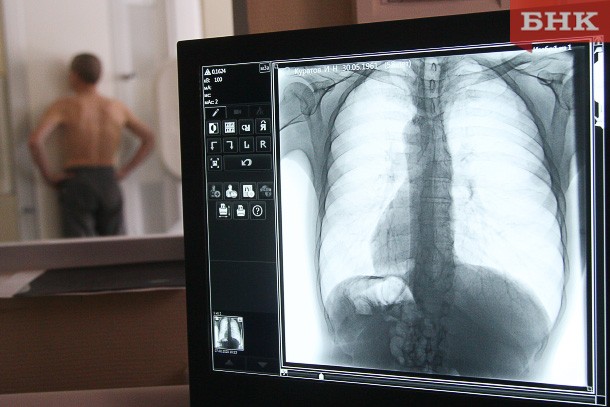

Врач назвал способы восстановить легкие после коронавируса

Врач-пульмонолог, профессор РАН Кирилл Зыков рассказал, как восстановить легкие после коронавируса. По его словам, переболевшим курильщикам в первую очередь следует отказаться от вредной привычки.

Кроме того, после болезни пациентам необходимо пройти полноценную реабилитацию работы органов дыхания, подчеркнул профессор. В нее входят комплексные тренировки, сочетающие выраженную нагрузку с менее активными упражнениями. Для достижения результата не менее важно придерживаться сбалансированной диеты.